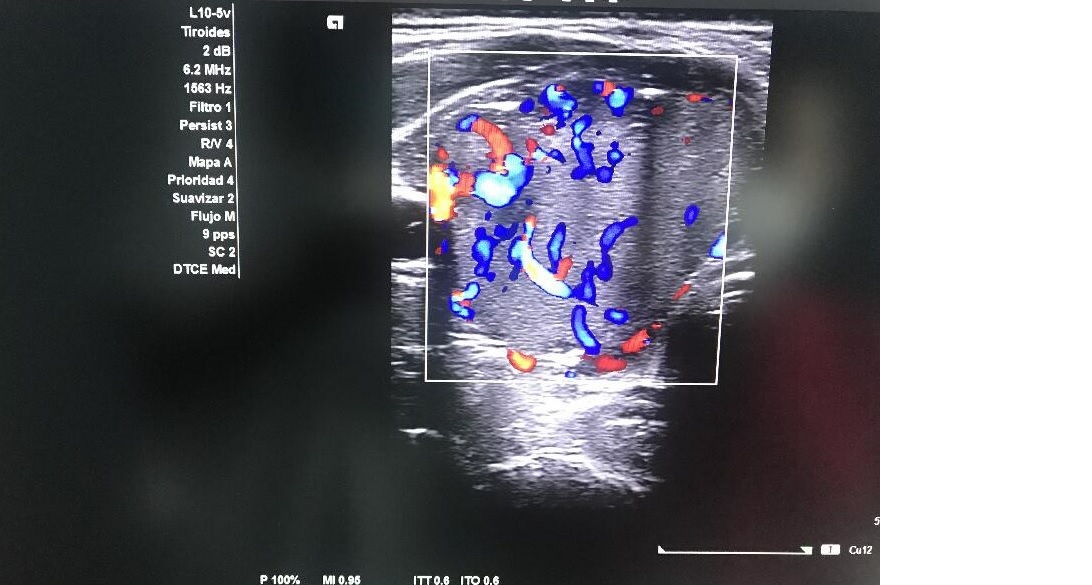

Ecografía tiroidea: Glándula tiroidea con ecoestructura homogénea en LTD con nódulo sólido en LTI con ocupación completa, hiperecogénico, bien delimitado con unas dimensiones de 3,5 x 3,5 x 4 con macrocalcificación en tercio superior con sombra acústica con vascularización de predominio periférico sin adenopatías cervicales.